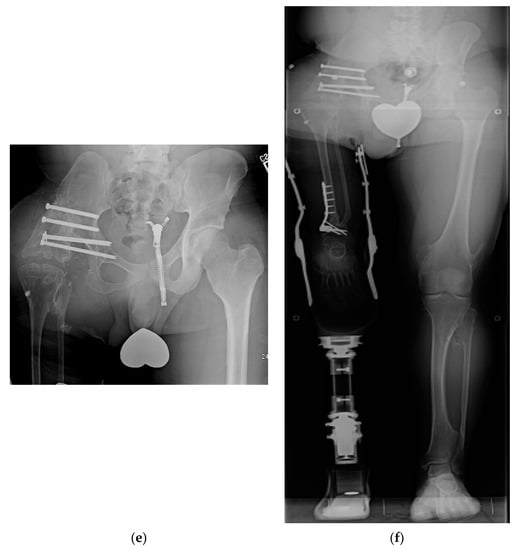

Figure 5.

(a) Illustration of CFD Paley type 3c. There is an ankylosed knee with a small distal femoral remnant. (b) Illustration showing the femoral head is enucleated to make room for the femoral condyle or tibial plateau in the acetabulum. (c) Paley–Winkelmann rotationplasty illustration, inserting the femoral condyle remnant into the acetabulum secured with a hip tethering suture. (d) AP pelvis radiograph of a 12-year-old girl with CFD Paley type 3c. (e) Standing long radiograph of same girl showing the ankle is at the level of the opposite knee. (f) AP pelvis radiograph of same girl after Paley–Winkelmann rotationplasty with femoral condyle in the acetabulum. The tethering suture anchor is seen. (g) Standing radiograph of same girl 5 years after Paley–Winkelmann rotationplasty. She has excellent function of the new hip joint and can walk and run with very minimal limp.